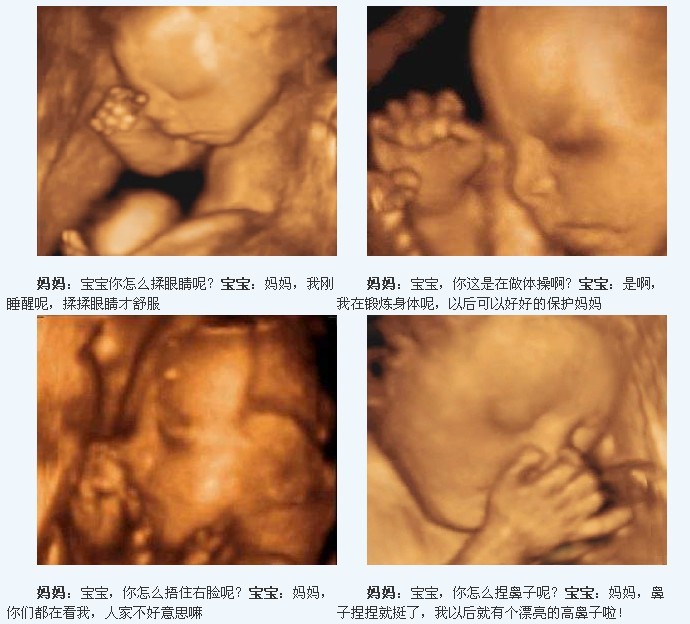

孕晚期八个月的四维图

怀孕八个月,已经开始进入孕晚期,小宝贝也在为出生做着后的准备,此时胎儿的身长大约42厘米,胎重也已将近2000克。那么孕八个月胎儿的四维彩超图片是什么样的呢?

通过彩超图,我们可以看到胎儿已经长出了满头的头发或者说绒毛,脚趾甲也全部长出来了。小宝贝的皮肤变得比以前透明和粉红,因为脂肪层在皮肤下面沉积了。胎宝宝的肺和胃肠功能接近成熟,已具备呼吸能力,能分泌消化液。他喝进的羊水,经过膀胱再排回羊水中。外形和内脏都大致完善,胎毛减少,皮肤为淡红色,胎脂较多,皱纹亦多。

胎儿的脑、胃肠、肺,肾发育接近成熟,听、视、嗅、味、触五种感觉器官也很发达了。胎位此时已固定,正常位置是:头朝下,臀向上的屈曲姿势。若宝宝在此时出生,只要精心呵护和养育,是可以健康成长的。